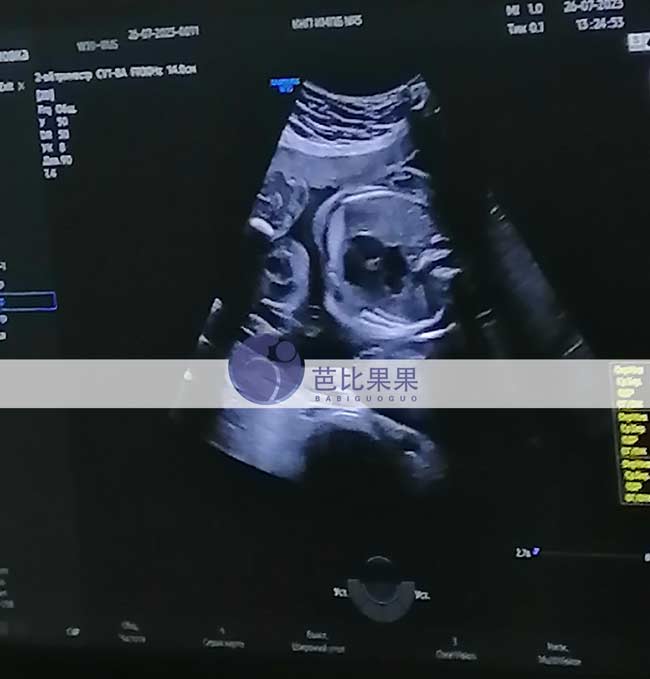

芭比果果三个乌克兰试管助孕家庭的试管妈妈来医院做产检

芭比果果三个乌克兰试管助孕家庭的试管妈妈来医院做产检,其中两位做B超检查,一位常规孕检,妈妈们都顺利通过了检查。